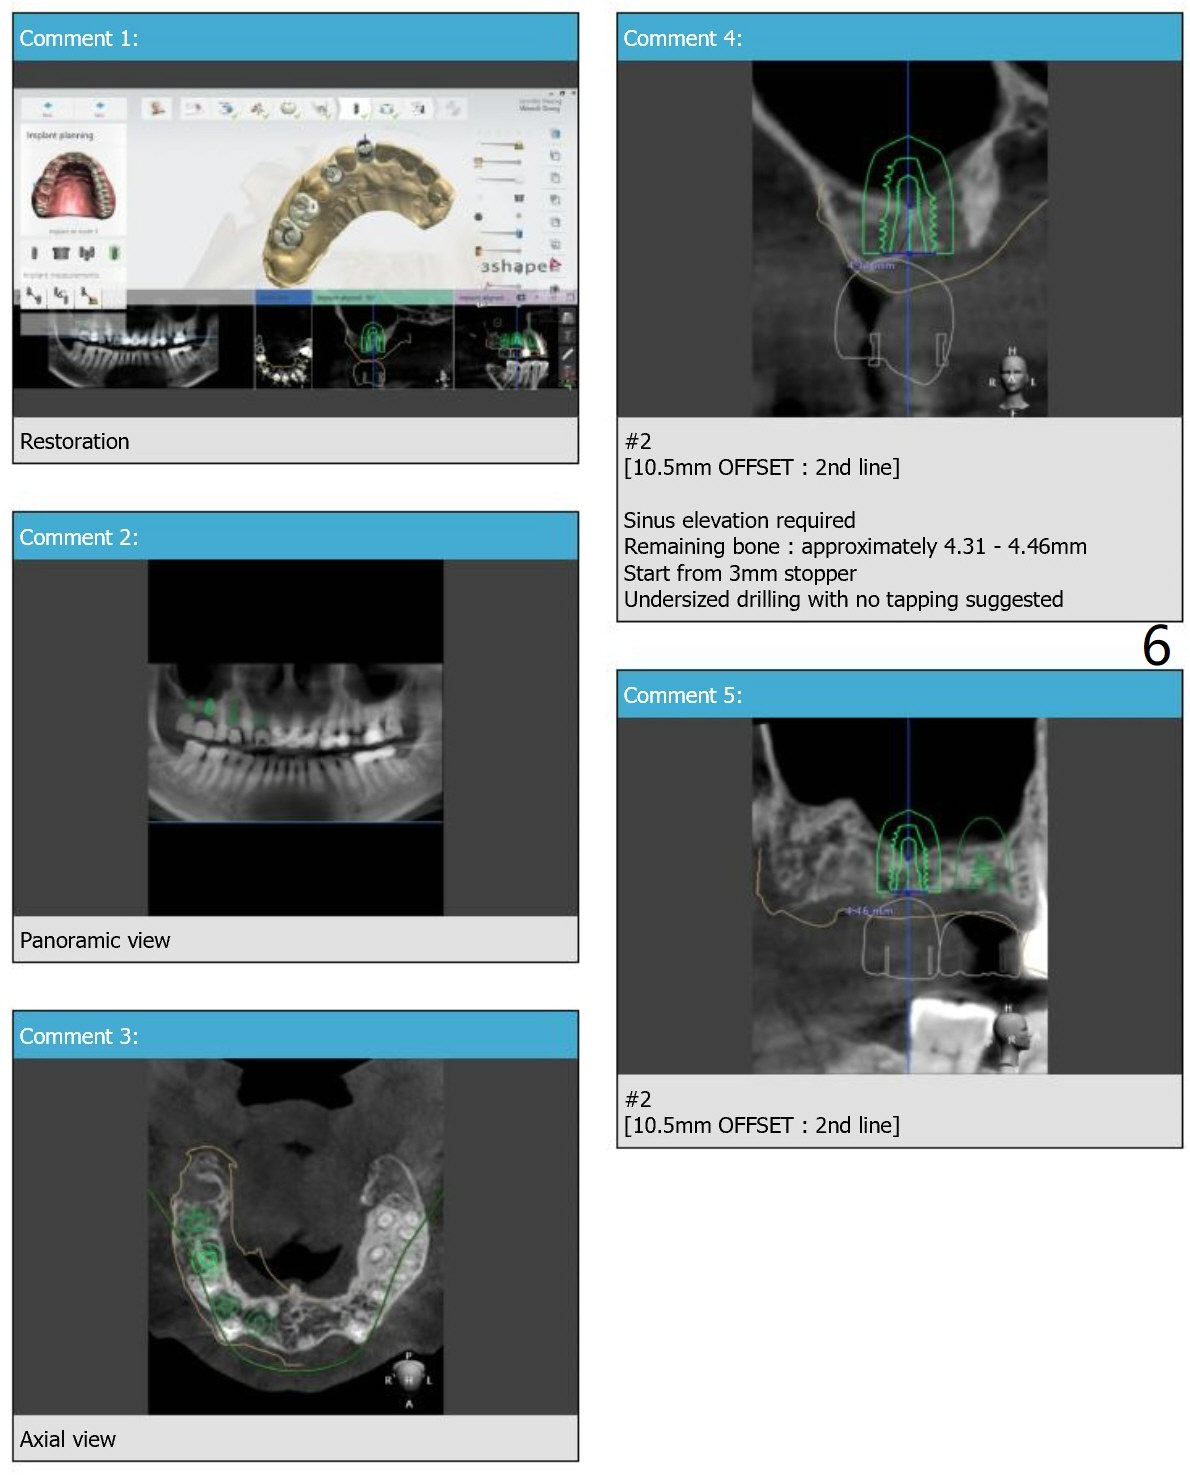

This case requires both narrow and regular navi guide kits and DIO 1-piece implant kit as well as DIO Sinus kits (regular and guided).

Also autoclave DIO guided sinus lift kit and prepare PRF.